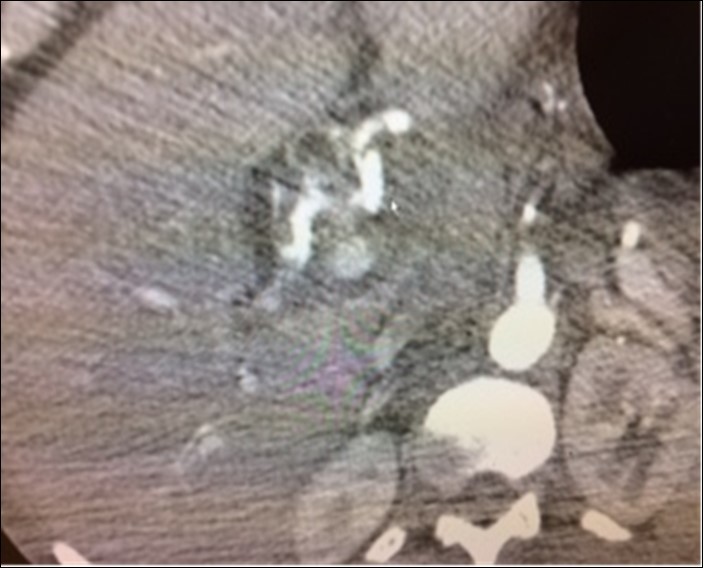

A 50 year old immune compromised patient was admitted to Bayonne Hospital on July 15, 2018, with severe gastrointestinal bleeding and anemia requiring six units packed red cells, two units of platelets and 2 units of fresh frozen plasma. Endoscopy revealed massive upper GI bleeding from duodenal ulcer. Epinepherine injection of the ulcer did not stop the bleeding. Percutaneous arteriogram revealed an aneurysm of the right hepatic artery bleeding into the first part of the duodenum wall. It was embolized, Figure 4. Past history revealed AIDS, Syphilis and tuberculosis. He had been on ventilator which was discontinued several days later. He is still hospitalized to treat his infections and a great deal of confusion, six weeks later. He is presumed deceased.